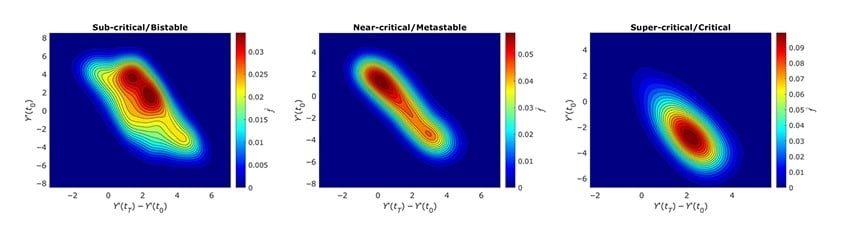

Функции плотности вероятности для случаев бистабильного, метастабильного и критического состояний ДНК / © Пресс-служба ПНИПУ

— Ключевым шагом моделирования стало введение трех разных режимов, в которых может находиться каждый участок ДНК: стабильного, неустойчивого и критического. Мы предположили, что они отражают фундаментальные фазы в жизни генома, влияющие на сценарии определения клеточной судьбы. Кроме того, мы определили структурный параметр, от которого зависит, в каком из этих трех состояний находятся фрагменты ДНК. В стабильном состоянии участок «закрыт», в неустойчивом он готов переключиться от малейшего сигнала, а в критическом открывается и может запустить цепную реакцию, которая способна перестроить активность по всему геному, — объяснил Александр Никитюк, доцент кафедры «Математическое моделирование систем и процессов» ПНИПУ.

Моделирование подтвердило, что когда участки начинали открываться, вся молекула начинала сама «подталкивать» соседние участки к тому же. Кроме того, численные результаты показали, что ДНК ведет себя как единый механизм, а преобразование в одном домене запускает волну скоординированных изменений. Этот кооперативный эффект объясняет, как клетка может одновременно переключать тысячи генов, быстро меняя свое состояние — например, начиная делиться или, наоборот, стареть.

Чтобы проверить свои расчеты, ученые сопоставили предсказания своей разработки с реальными экспериментальными данными по работе с разными типами клеток — от эмбриональных до раковых. Статистические показатели, которые дала их физическая модель, совпали с теми, что получили биологи ранее. Это доказывает, что предложенный механизм действительно отражает универсальные принципы, лежащие в основе регуляции генома.